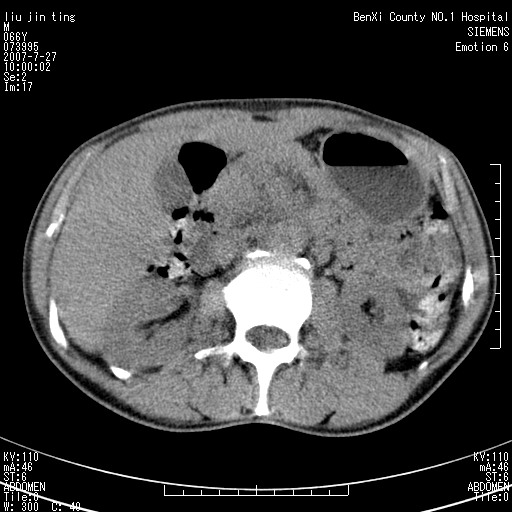

腹痛,背痛,无恶心呕吐,不黄,彩超示胰腺钩癌,ct扫描病灶平扫30-40hu,增强后动脉期40--60hu,静脉期50-68hu,真的是钩突上的么?您要试一试么?

动脉期

静脉期

沿着肠系膜上动脉呈匍匐性生长的软组织肿块,形态不规则,包绕肠系膜上动脉,呈明显强化,考虑来源于肠系膜的恶性肿瘤

沿着肠系膜上动脉呈匍匐性生长的软组织肿块,形态不规则,包绕肠系膜上动脉,呈轻-中度强化,考虑来源于肠系膜的恶性肿瘤。

钩突是正常的,只见腹膜后淋巴结的肿大,考虑淋巴瘤或转移可能。

支持!恶性纤维组织细胞瘤可能,与淋巴瘤及淋巴结转移鉴别(腹主动脉周围清晰,其他部位亦未见明显肿大淋巴结)。